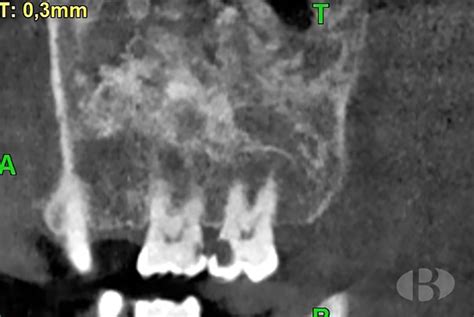

Desde un punto de vista radiográfico, las lesiones de displasia fibrosa se caracterizan por un aspecto de vidrio deslustrado debido a la mezcla de elementos óseos y fibrosos. La densidad radiográfica de la lesión dependerá de la proporción relativa de estos elementos. Así pueden adoptar un patrón esclerótico, quístico (lítico) o mixto. La variante esclerótica constituye un 35% de los casos descritos y tiende a localizarse en la base del cráneo. La variante mixta es la más frecuente (40% de los casos), y el patrón quístico es el menos frecuente.

Por ello es necesario un diagnóstico, además de clínico, basado en la imagen radiográfica (ya casi no utilizada) y más frecuentemente de TC, donde se describen varias formas (Schumberger, 1946):

- Pagetoide: expansión ósea con islas dispersas de formación ósea en campo de baja atenuación

- Esclerótica: apariencia homogénea con patrón en "vidrio esmerilado"

- Cística: lesión bien definida de baja atenuación con borde esclerótico en patrón de "cáscara de huevo"

TC mostrando displasia fibrosa con apariencia de vidrio esmerilado.